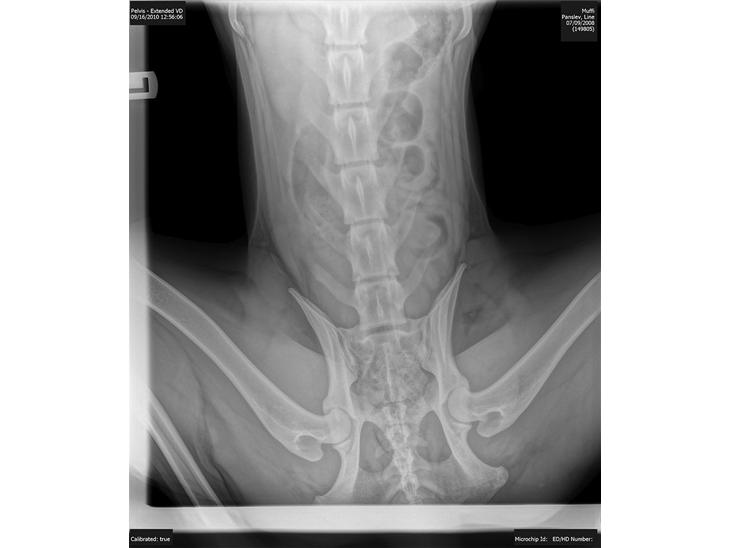

Øh, jeg har ikke forstand på hofter, men har han hd. for mig ser det ud som om den højre ser mærkelig ud, og mindre end den venstre?